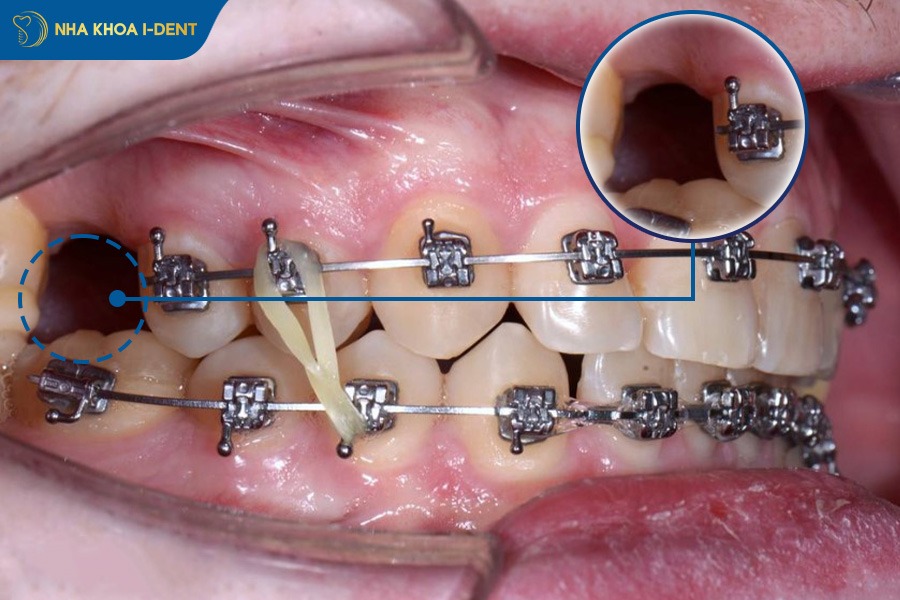

- Sử dụng minivis: Minivis được cắm vào xương hàm để tạo điểm neo chắc chắn, giúp bác sĩ kéo toàn bộ khối răng về phía sau một cách hiệu quả. Kỹ thuật này thường được áp dụng thay thế cho nhu cầu nhổ răng cối nhỏ trong các ca hô nhẹ đến nặng.